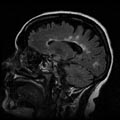

Λονδίνο: Ένας νέος τρόπος θεραπείας της σκλήρυνσης κατά πλάκας ενδεχομένως να είναι υπό ανακάλυψη, αν τα εντυπωσιακά αποτελέσματα που διαπιστώθηκαν σε πειραματόζωα βρουν αντίκρισμα και στους ανθρώπους, σύμφωνα με στοιχεία που δημοσιεύονται στο επιστημονικό έντυπο Science.